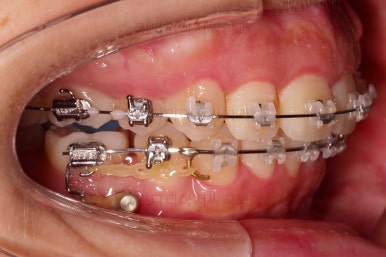

아랫니도 발치를 하고요.

윗니는 아랫니가 뒤로 들어가는 만큼 더 뒤로 밀어야 되기 때문에 미니스크류를 이용해서 뒤로 당기기를 해줍니다.

다만, 이 시점에서 주의할 점은 입이 너무 들어가지 않도록 해야 하는 점인데요.

공간이 적절하게 줄어들었을 시점에서 얼굴모습을 평가하여 이제는 너무 들어가지 않았는지 체크합니다.

이번 환자분은 아랫니 발치 공간이 절반 쯤 줄었을 시점부터 해당 시점의 얼굴모습을 만족하셔서 앞니를 뒤로 당기는 방향은 적절하지 않았습니다.

이 때 대신 선택하는 방법이 어금니를 앞으로 끌고와서 남은 발치 공간을 없애는 방법인데요.

마찬가지로 미니스크류가 사용됩니다.

밀고 당기기와 디테일을 더 정리한 뒤 부산무턱교정치과 마무리를 하게 됩니다.

교합, 과개교합 모두 좋아졌고요.

발치 공간도 깔끔하게 닫히고 종료했습니다.